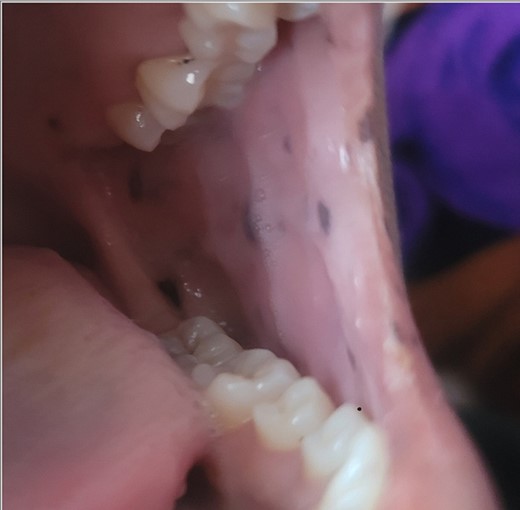

A 28-year-old female patient arrived at the emergency department complaining of intermittent colicky abdominal pain and presenting with tachycardia. She had not passed stool or flatus for 3 days, accompanied by vomiting. Upon physical examination, mucocutaneous hyperpigmentation was observed in the oral cavity (Fig. 1), along with a distended abdomen and increased bowel movement, which were hypertympanic on percussion. Initial investigations, including abdominal and pelvic ultrasonography, abdominal X-rays in erect and supine positions (Fig. 2), chest X-ray and computed tomography scan, revealed a 3-cm diameter, a 5 air level fluid, a U-shaped distension with 3.2-cm diameter mural thickening, mesenteric fat infiltration, and pneumatosis. There were no signs of peritonitis, and laboratory values fell within normal limits.